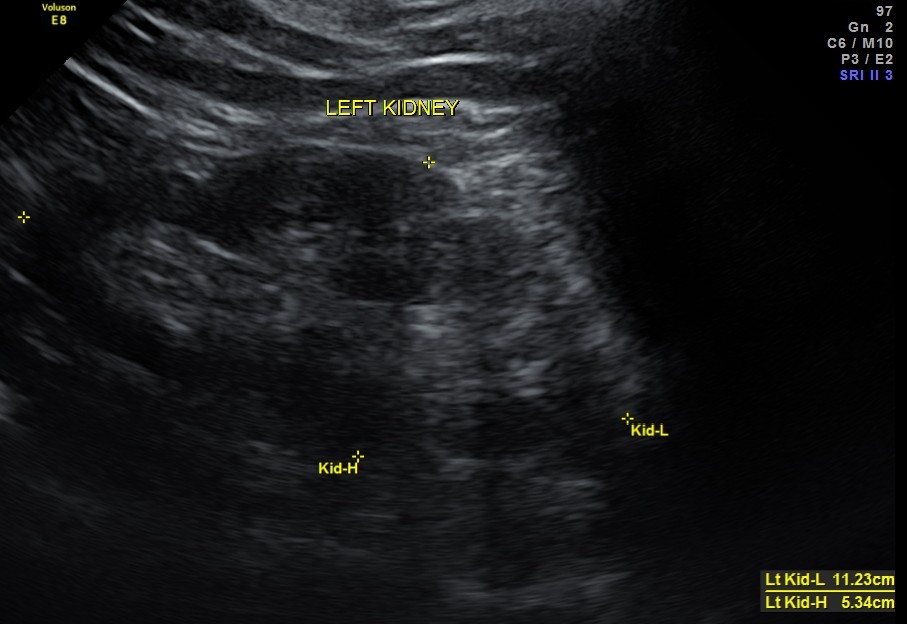

Liver, gall bladder , pancreas, spleen and the left kidney were normal . The prostate showed mild enlargement.